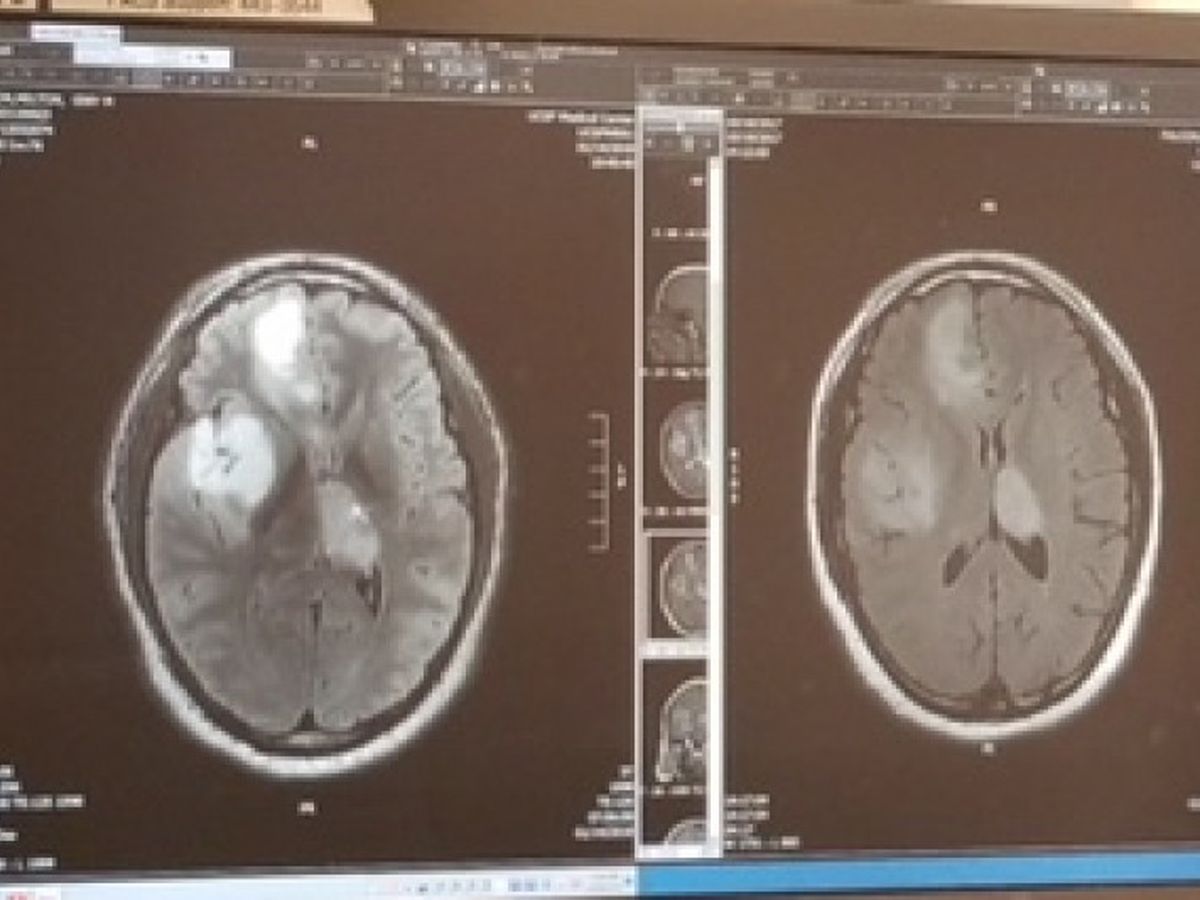

I worked in restaurants and as a delivery driver. One day, I started to feel ill, went to the doctor... got diagnosed

with Anaplasic Astrocytoma in several areas of my brain, specifically I have 4 malign tumors (cerebral cancer).

un dia empece a sentir malestares, fui al medico y fui diagnosticado con astriocitoma anaplasico, en diferentes areas de mi cerebro, especificamente tengo 4 tumores malignos (cancer en el cerebro).